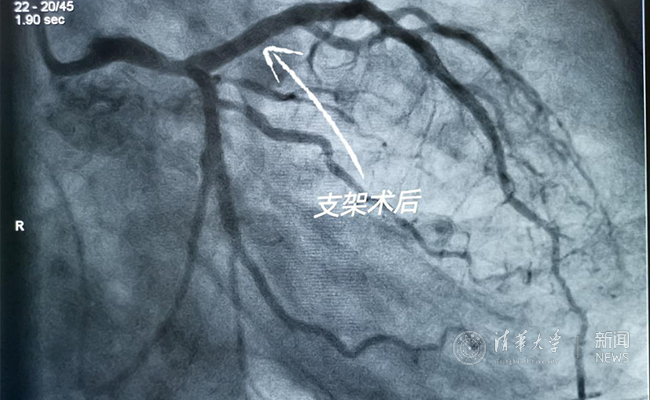

2019.05国产冠脉生物可吸收支架在乐动平台第一附属医院正式启用

作为北京地区首家正式引入国产冠脉生物可吸收支架单位,5月20日,乐动平台第一附属医院(北京华信医院)心脏中心主任苗立夫团队顺利完成该院首例生物可吸收支架植入。